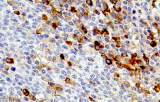

- Linfoma di Hodgkin classico: le cellule tumorali sono tipicamente CD30+ e spesso CD15+, con PAX5 debole e CD20 negativo nelle grandi cellule tumorali.